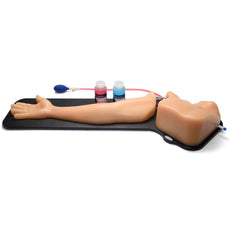

The model is of a supine adult male and extends from the upper buttocks to the lower neck. Positioned in the mid scapulary line, the ultrasound tissue insert contains chest wall superficial tissue, 6th, 7th, 8th, and 9th ribs and intercostal spaces, pleural cavity with lung and atelectatic lung, diaphragm, and superior spleen. The pleural fluid collections allow users to develop and refine their ultrasound guided thoracentesis skills. This model is extremely realistic and is self-healing offering you superb training with a low cost of ownership.

The ultrasound tissue insert offers extremely realistic sonographic imaging characteristics is designed for guiding the placement of needles and small catheters (18-21 gauge and associated catheter kits). Blue Phantom simulated human tissue is very realistic and ultra-durable; excellent for repeated training in skills associated with ultrasound guided thoracentesis procedures. Positive fluid flow offers users feedback when pleural effusions are accurately accessed. The fluid is easily refilled using a quick fill luer lock or can be connected to an I.V. reservoir for continuous fluid delivery. Users can also learn to avoid accessory structures as the spleen, diaphragm and lung.

Ultrasound imaging skills include; using ultrasound system controls, transducer positioning and movement, recognition of thoracic anatomy, lung, diaphragm, anterior spleen and pleural effusions, using ultrasound to target the appropriate fluid pockets for needle guidance, and performing an ultrasound guided thoracentesis procedure. Our self-healing tissue will allow you to repeatedly perform ultrasound guided thoracentesis procedures without giving second thought to wearing out the tissue or calculating the cost per cannulation. You can expect unmatched durability from our tissue. This ultrasound training mannequin is constructed using Blue Phantom’s patented ultra-durable tissue and is extremely realistic in ultrasound imaging characteristics and feels like real human tissue. Our self-healing tissue will withstand tremendous use and will save you money by dramatically reducing the necessity for purchasing replacement parts. Constructed using Blue Phantom simulated tissue which match the acoustic characteristics of real human tissue so when you use your ultrasound system on our training models, you experience the same quality you expect from imaging patients in a clinical environment.

Blue Phantom's mid-scapular thoracentesis ultrasound training model is specifically designed for ultrasound guided thoracentesis procedures. This ultrasound training phantom aids users in developing and practicing the skills associated with a mid scapulary approach to ultrasound guided thoracentesis procedures. This model is excellent for assisting clinicians in gaining proficiency in using ultrasound to identify and guide needle and small gauge catheter insertions in a patient with pleural effusions for diagnostic and/or therapeutic purposes.The model is of a supine adult male and extends from the upper buttocks to the lower neck. Positioned in the mid scapulary line, the ultrasound tissue insert contains chest wall superficial tissue, 6th, 7th, 8th, and 9th ribs and intercostal spaces, pleural cavity with lung and atelectatic lung, diaphragm, and superior spleen. The pleural fluid collections allow users to develop and refine their ultrasound guided thoracentesis skills. This model is extremely realistic and is self-healing offering you superb training with a low cost of ownership.

The ultrasound tissue insert offers extremely realistic sonographic imaging characteristics is designed for guiding the placement of needles and small catheters (18-21 gauge and associated catheter kits). Blue Phantom simulated human tissue is very realistic and ultra-durable; excellent for repeated training in skills associated with ultrasound guided thoracentesis procedures. Positive fluid flow offers users feedback when pleural effusions are accurately accessed. The fluid is easily refilled using a quick fill luer lock or can be connected to an I.V. reservoir for continuous fluid delivery. Users can also learn to avoid accessory structures as the spleen, diaphragm and lung.

Ultrasound imaging skills include; using ultrasound system controls, transducer positioning and movement, recognition of thoracic anatomy, lung, diaphragm, anterior spleen and pleural effusions, using ultrasound to target the appropriate fluid pockets for needle guidance, and performing an ultrasound guided thoracentesis procedure. Our self-healing tissue will allow you to repeatedly perform ultrasound guided thoracentesis procedures without giving second thought to wearing out the tissue or calculating the cost per cannulation. You can expect unmatched durability from our tissue. This ultrasound training mannequin is constructed using Blue Phantom’s patented ultra-durable tissue and is extremely realistic in ultrasound imaging characteristics and feels like real human tissue. Our self-healing tissue will withstand tremendous use and will save you money by dramatically reducing the necessity for purchasing replacement parts. Constructed using Blue Phantom simulated tissue which match the acoustic characteristics of real human tissue so when you use your ultrasound system on our training models, you experience the same quality you expect from imaging patients in a clinical environment.

- Excellent for training clinicians in the psycho-motor skills associated with ultrasound guided thoracentesis procedures

- Positive fluid flow offers users immediate feedback when pleural effusion fluid is accurately accessed

- Pleural fluid that is removed during thoracentesis procedural training is easily refilled using a quick fill port – or automatically refilled using I.V. bag reservoir

- 1 bottle (BRS-183 - 235 mls) of thoracentesis pleural replacement fluid included with model purchase

DIMENSIONS: Size: 17” long x 11” wide x 17” high (43 cm x 28 cm x 43 cm)

Weight: 20 lbs. (9 kg)